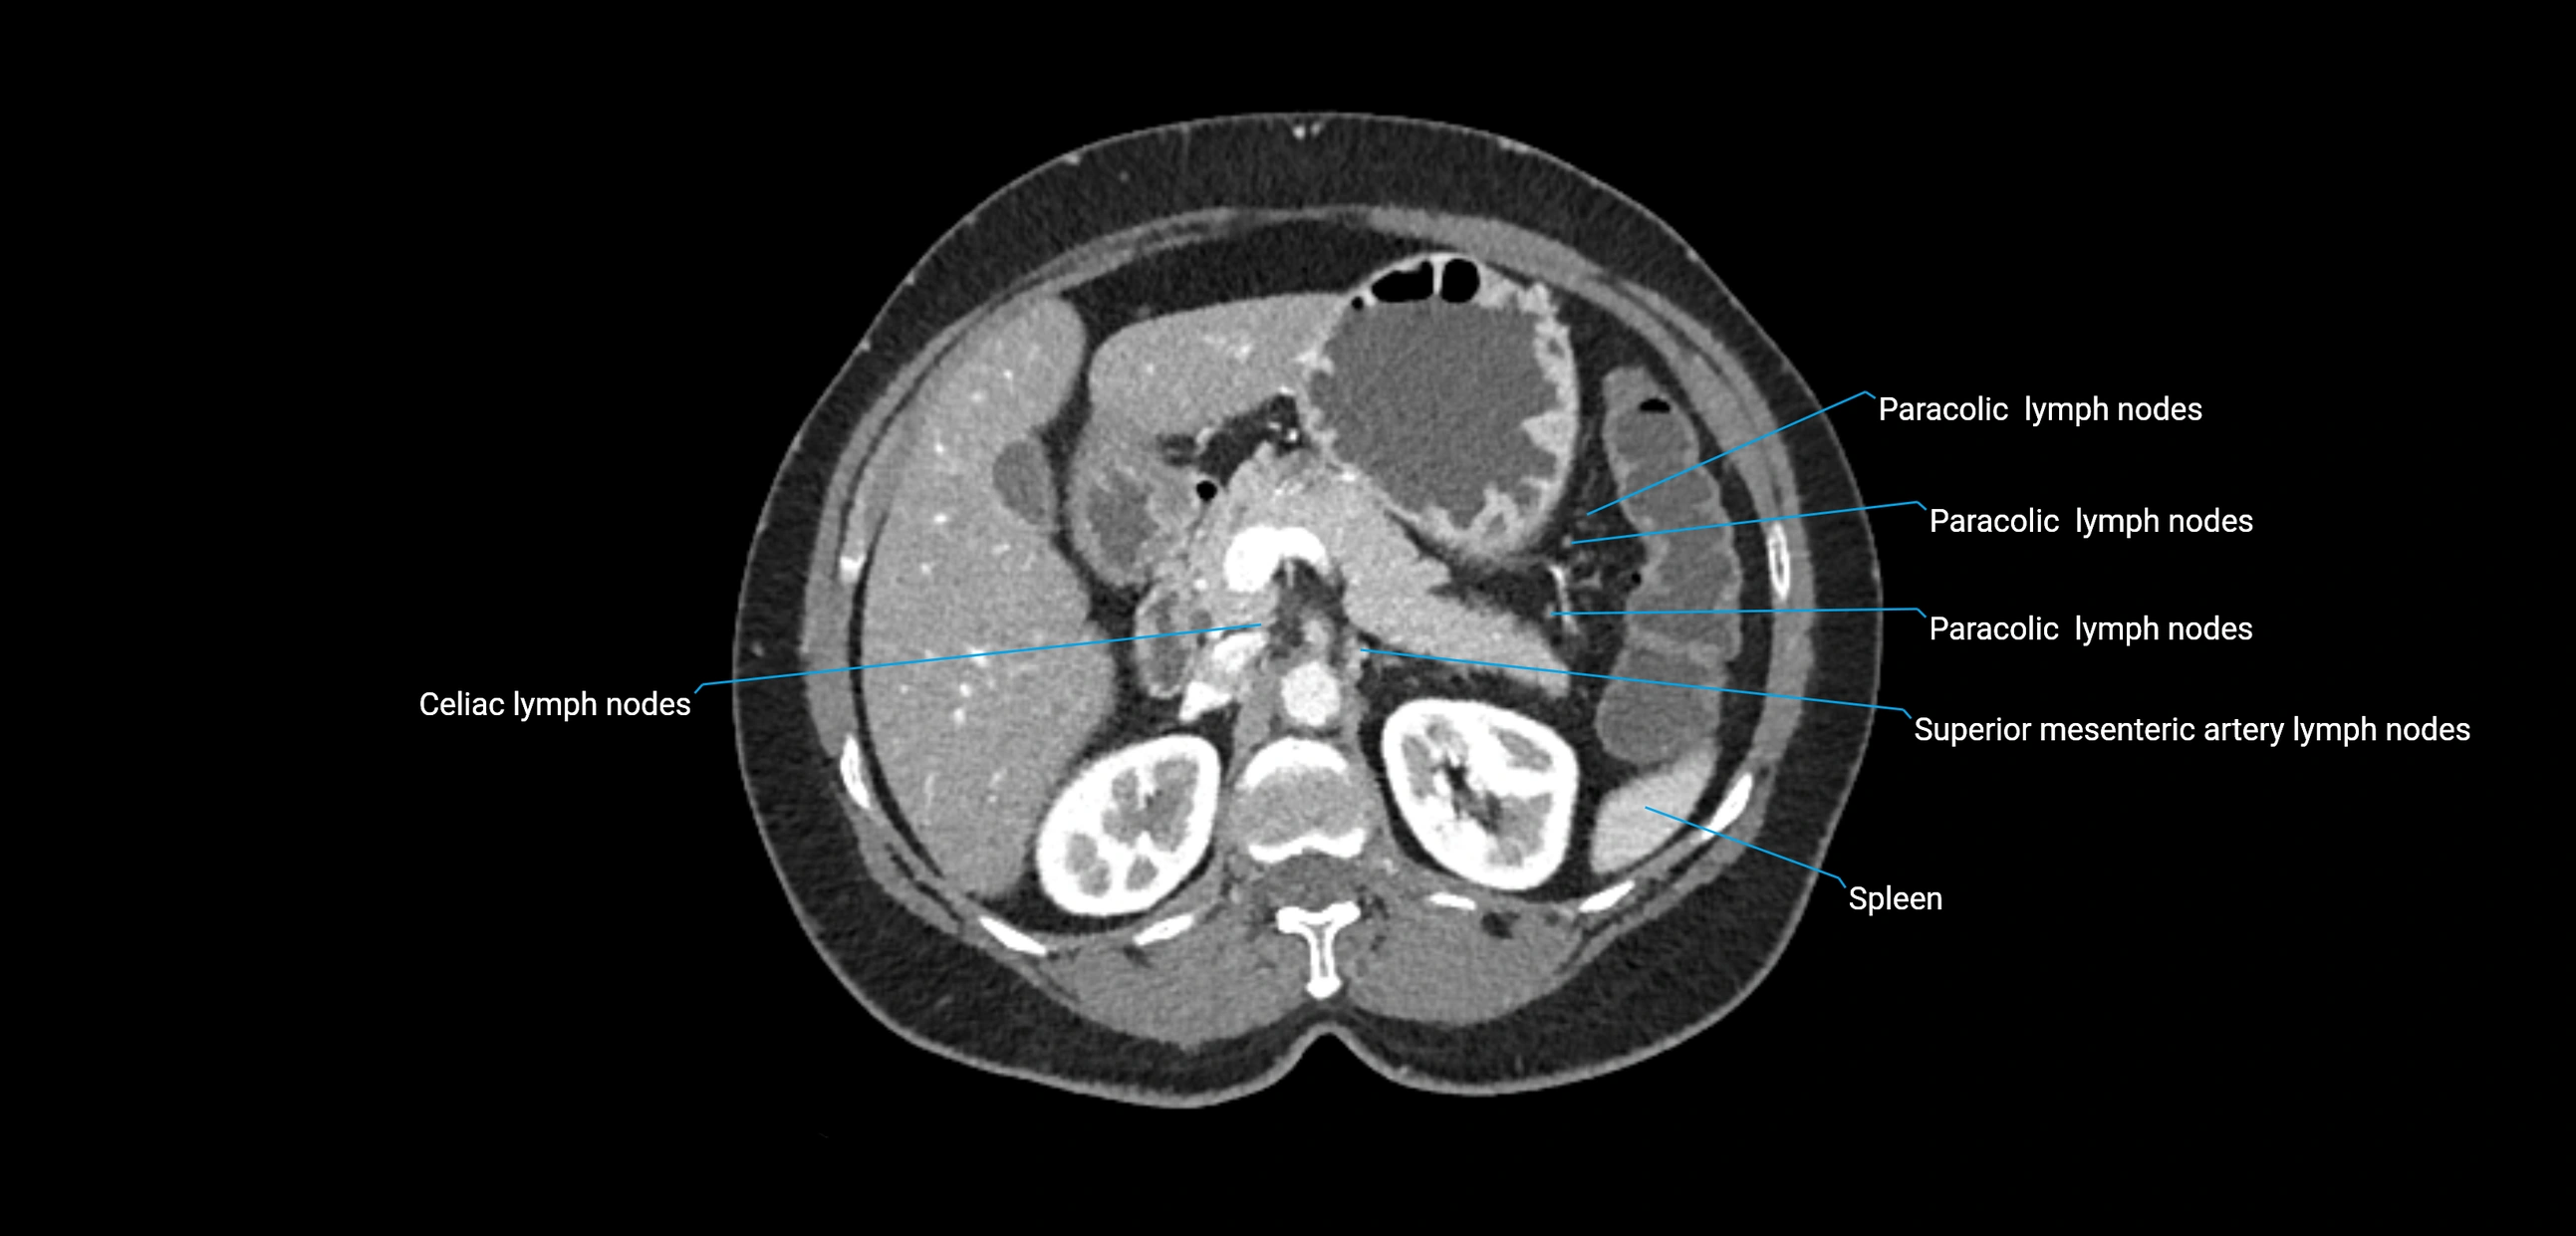

CT Appearance

CT Pre-Contrast:

• Nodes appear as soft-tissue density nodules adjacent to the aorta and IVC

• Calcification may be seen in chronic infections (e.g., tuberculosis)

CT Post-Contrast:

• Normal nodes enhance homogeneously

• Malignant nodes may show heterogeneous enhancement, central necrosis, or conglomerate formation

• Size >1 cm short axis is suspicious, though morphology and distribution are equally important